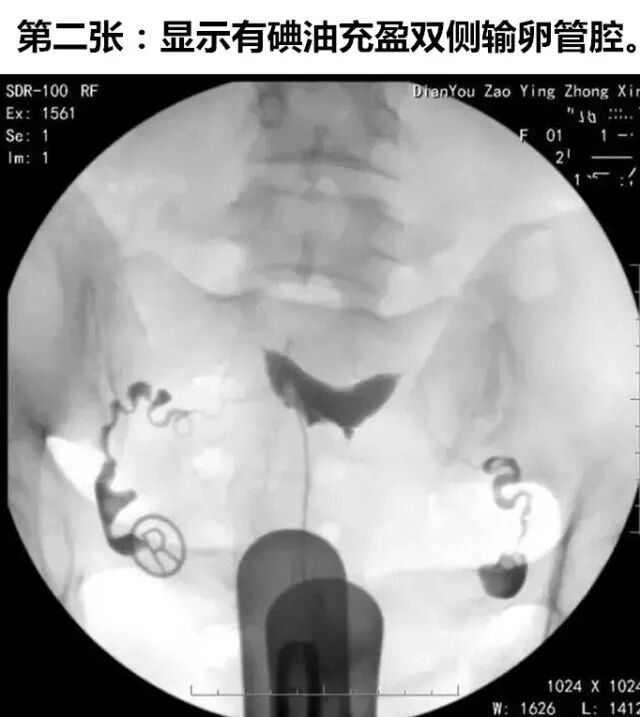

实时动态子宫输卵管碘油造影是将传统的造影改良,使患者无痛,将球囊导管置入宫颈内口,注入液体充盈球囊堵住宫颈内口后,将碘化油经导管缓慢注入宫腔,在X光透视下,动态观察碘油逐渐膨胀宫腔,流入输卵管,经伞端流入盆腔的全过程。在操作后的12~24小时,再拍一张延迟涂抹片,观察碘油在盆腔内的弥散情况。

如下图所示,这是一张正常的延迟涂抹片,碘油在盆腔内均匀弥散。